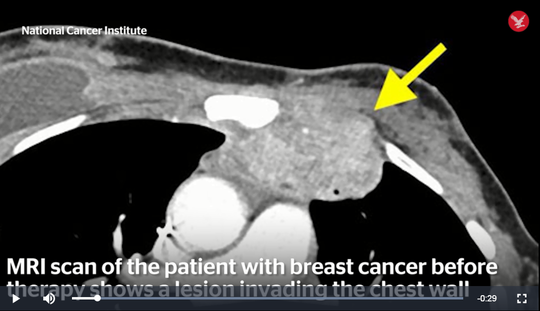

Khối u rất lớn trong ngực bà Perkins thể hiện trên phim MRI - ảnh cắt từ clip của NCI |

Không còn gì để mất, bà Perkins quyết định tham gia thử nghiệm của NCI. Các nhà khoa học sử dụng tế bào T – chính là tế bào miễn dịch trong cơ thể con người, thực hiện một số thay đổi trong nó. Các tế bào được chỉnh sửa này được đưa trở lại cơ thể và kích thích hệ miễn dịch sinh ra phản ứng mạnh mẽ đối với khối u.